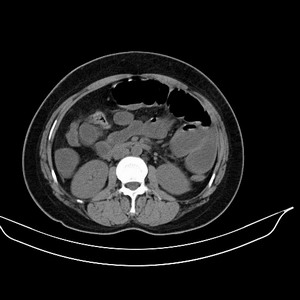

女 42岁 子宫肌瘤于外院术后两天,感腹胀。x线提示肠梗阻。

子宫肌瘤于外院术后两天,出现肠扭转梗阻,很明显。但右下腹部出现的线状高密度,是什么呢?有什么手术会有这样的物品呢?不会把电刀的导线遗留在腹腔吧!?

结果:术后纱布遗留,术后麻痹性肠梗阻肠梗阻

上面的图像是我们从手术室拿来的纱布做了个ct平扫,发现纱布里确实存在有一条致密影。后得知致密影是为防止手术时纱布遗留而设计。关腹时怀疑纱布遗留可做个床边透视或拍片可明确。